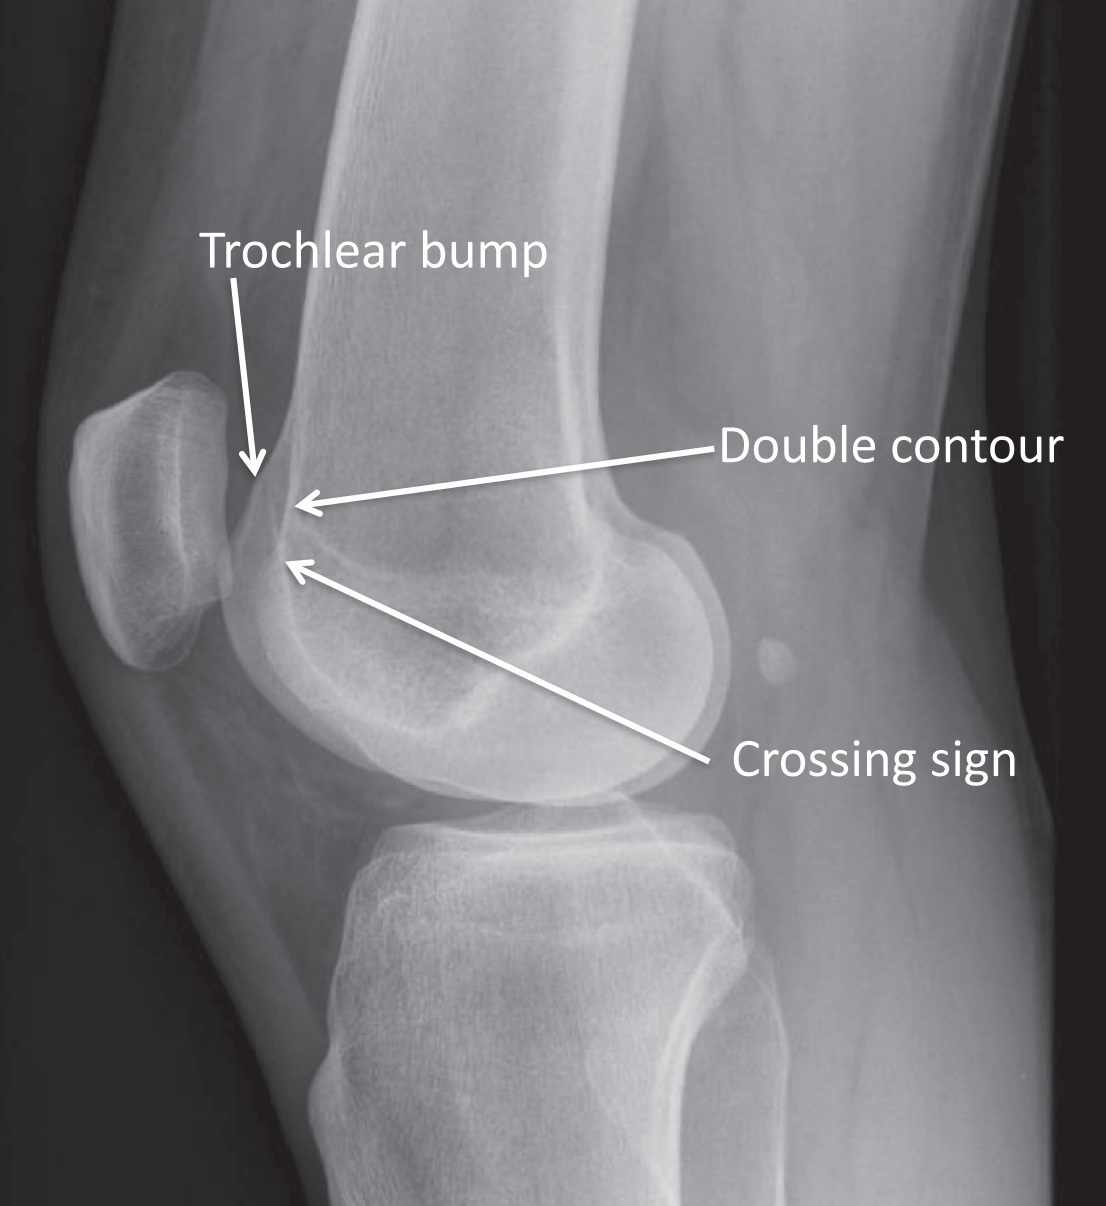

Troclea dysplasi Dejour type A, B, C og D.